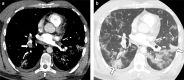

Objectives: Early in the coronavirus 2019 (COVID-19) pandemic, a high frequency of pulmonary embolism was identified. This audit aims to assess the frequency and severity of pulmonary embolism in 2020 compared to 2019.

Methods: In this retrospective audit, we compared computed tomography pulmonary angiography (CTPA) frequency and pulmonary embolism severity in April and May 2020, compared to 2019. Pulmonary embolism severity was assessed with the Modified Miller score and the presence of right heart strain was assessed. Demographic information and 30-day mortality was identified from electronic health records.

Results: In April 2020, there was a 17% reduction in the number of CTPA performed and an increase in the proportion identifying pulmonary embolism (26%, n = 68/265 vs 15%, n = 47/320, p < 0.001), compared to April 2019. Patients with pulmonary embolism in 2020 had more comorbidities (p = 0.026), but similar age and sex compared to 2019. There was no difference in pulmonary embolism severity in 2020 compared to 2019, but there was an increased frequency of right heart strain in May 2020 (29 vs 12%, p = 0.029). Amongst 18 patients with COVID-19 and pulmonary embolism, there was a larger proportion of males and an increased 30 day mortality (28% vs 6%, p = 0.008).

Conclusion: During the COVID-19 pandemic, there was a reduction in the number of CTPA scans performed and an increase in the frequency of CTPA scans positive for pulmonary embolism. Patients with both COVID-19 and pulmonary embolism had an increased risk of 30-day mortality compared to those without COVID-19.